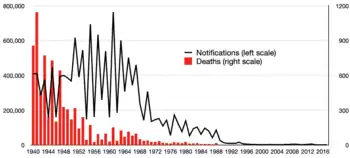

Europe

In England and Wales, though deaths from measles were uncommon, they averaged about 500 per year in the 1940s. Deaths diminished with the improvement of medical care in the 1950s but the incidence of the disease did not retreat until vaccination was introduced in the late 1960s. Wider coverage was achieved in the 1980s with the measles, mumps and rubella, MMR vaccine.[107]